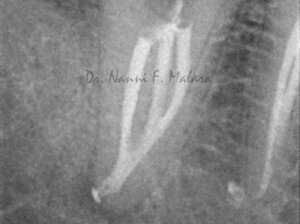

Molare affetto da lesione periapicale a carico di entrambe le radici (Alla radiografia si presentano come aree scure intorno alle radici)